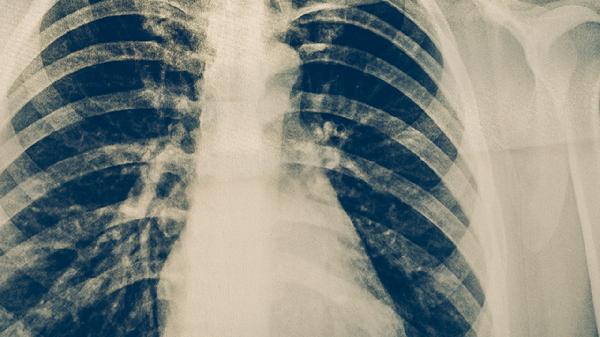

胸部CT是肺癌筛查和诊断的重要影像学手段,能清晰显示肺部病变的位置、大小、形态及与周围组织的关系。低剂量螺旋CT常用于高危人群筛查,普通CT可发现直径3毫米以上的肺结节,增强CT有助于判断纵隔淋巴结转移情况。对于疑似中央型肺癌,CT可观察到支气管狭窄或截断征象。